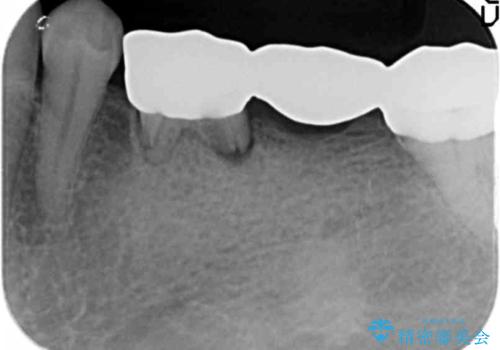

乳歯を使ってブリッジにしていましたが、支台歯が両方虫歯になっており、根が短くなって持たなくなった乳歯を抜いて、インプラントにすることになりました。

治療スケジュールとしては

①保存不可能な歯の抜歯

②6か月待つ

③インプラント埋入

④2か月待つ

⑤二次手術(APF)

⑥仮歯の装着

⑦最終的なセラミッククラウンの装着

となります。